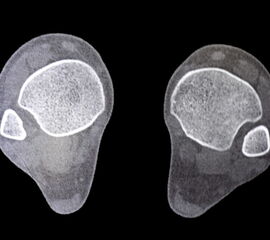

Computertomographie (CT)

Die CT-Diagnostik erlaubt eine kritischere Beurteilung des DTFG. Die Wertigkeit zur Beurteilung von Syndesmosenverletzungen wurde in diversen Studien untersucht. Die Kongruenz im distalen Tibiofibulargelenk sollte in den axialen Schichten beurteilt werden 39. Aufgrund der hohen physiologischen Varianz, ist ein Seitenvergleich empfehlenswert (Abb. 5). So können die anteroposteriore Translation, Rotation und Verkürzung des betroffenen DTFG im Vergleich zum gesunden DTFG verglichen werden 40.